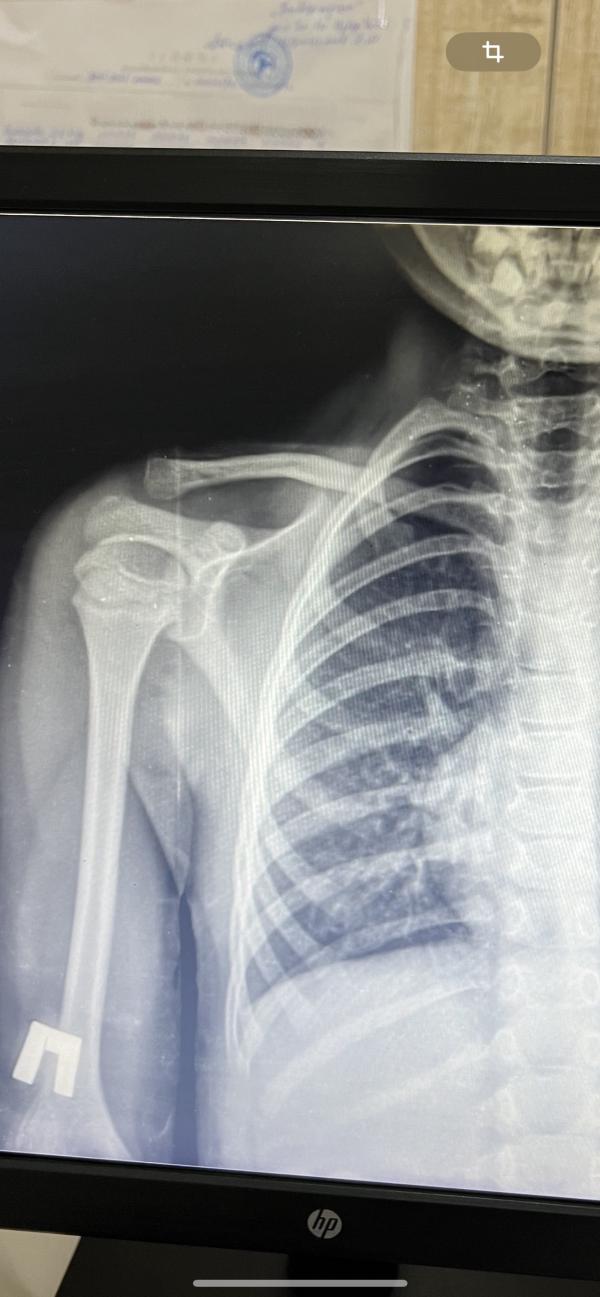

Доча упала с кухонки и ключицу повредила , на рентгене трещина без смещения . Был чуть бугорок . Врач сказал это мозоль после ушиба , так бывает мол пройдёт . У уже месяц прошел у нее так же бугорочек остался ((( я даже во второй раз пошла и спросила . Так напрягает меня . В годик тоже она повреждала ключицу аж с обеих сторон , тоже без смещения , но норм зажило . Кто нибудь сталкивался с таким? Это получается уже ломать и собирать снова надо будет ?(